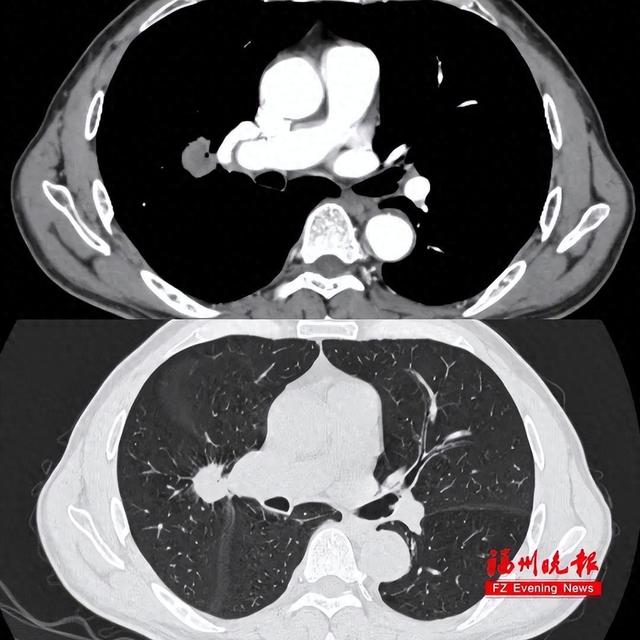

林主任在看过胸部CT后判定右肺2处结节均需尽快手术切除,但术前肺功能检查结果又让医生们犯了难。因为长期抽烟,廖先生的肺功能指标不足正常人的四成,完全不能满足手术麻醉的要求。

胸部CT可见肿瘤紧贴肺门大血管。